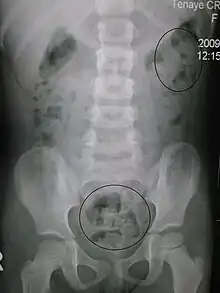

Constipation in a young child seen on X-ray. Circles represent areas of fecal matter (stool is white surrounded by black bowel gas).